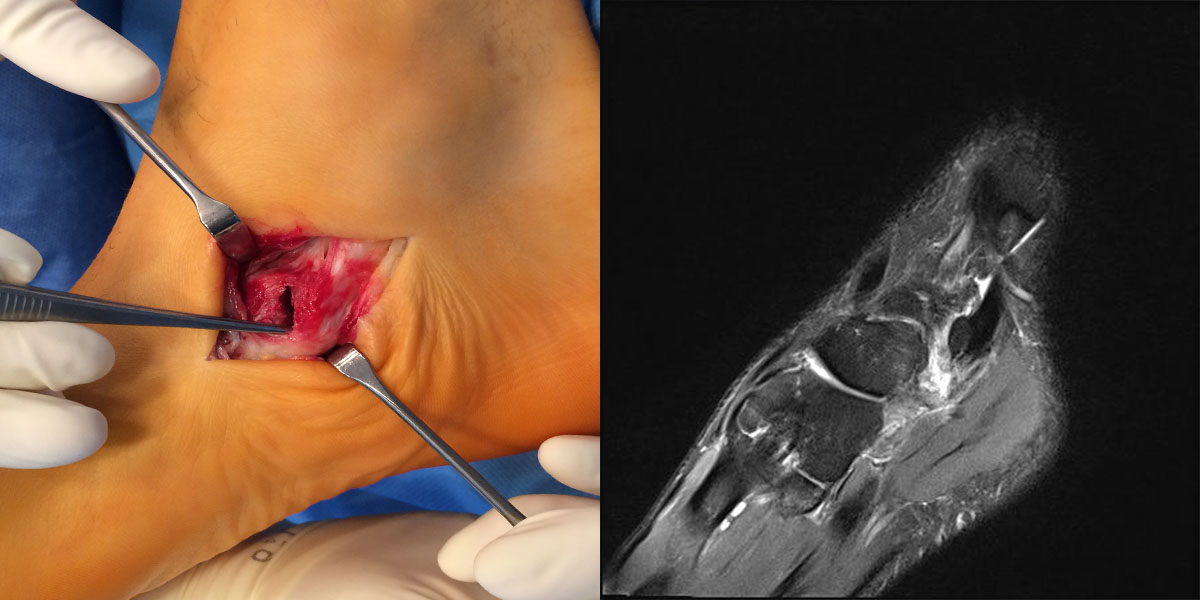

Direkte Traumazeichen wie ein Hämatom oder eine ausgeprägte Schwellung treten üblicherweise nicht auf, wobei vereinzelt auch bei einem adäquaten Trauma ein vollständiger Ausriss des Os tibiale externum beobachtet werden kann (Abb. 1).

Zum Lesen der Bildbeschreibung und zur Vollansicht bitte das Bild anklicken. Foto: Markus Walther

Resektion des Os tibiale externum bzw. Abtragung des medial prominenten Os naviculare cornutum und Refixation der Tibialis posterior Sehne am Os naviculare.

- Beim Herauslösen des Os tibiale externum sollten die kaudal zum Os naviculare verlaufenden Fasern der Tibialis posterior Sehne geschont werden. Somit wird eine vollständige Ablösung der Sehne vermieden. Grundsätzlich ist nur so viel des Sehnenansatzes abzulösen, wie zur Entfernung des Knochens notwendig.